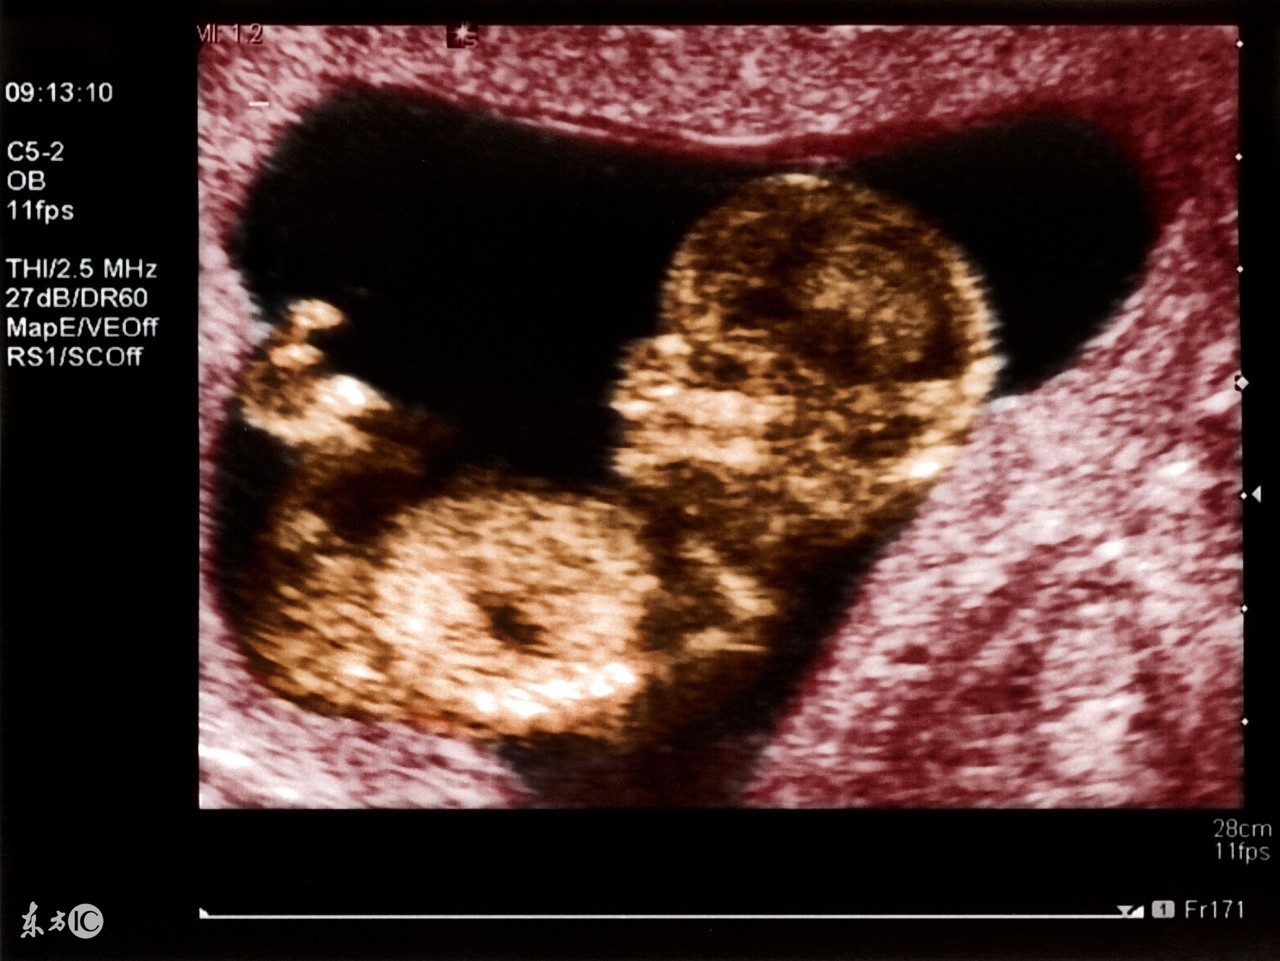

四维彩色超声诊断仪是目前世界上最先进的彩色超声设备。“4D”是“四维”的缩写。第四维是指时间这个矢量,所以也被称作实时三维。4D超声技术就是采用3D超声图像加上时间维度参数,该革命性的技术能够实时获取三维图像,超越了传统超声的限制。它提供了包括腹部、血管、小器官、产科、妇科、泌尿科、新生儿和儿科等多领域的多方面的应用。其结果是:能够显示您未出生的宝宝的实时动态活动图像,或者其它人体内脏器官的实时活动图像。

四维彩超就是四维成像技术(4D)能直观、立体显示*体器人官**的三维结构及动态、实时地观察立体结构,而以往的二维成像技术只能显示*体器人官**的某一切面。

在妇产科方面,四维彩超能够对胎儿进行超声检查能立体显示胎儿的颜色、面、各器官的发育情况,甚至胎儿在母体里的状态也可以观察到;对胎儿畸形,如唇裂、腭裂、骨骼发育异常、心血管畸形等能早期诊断。